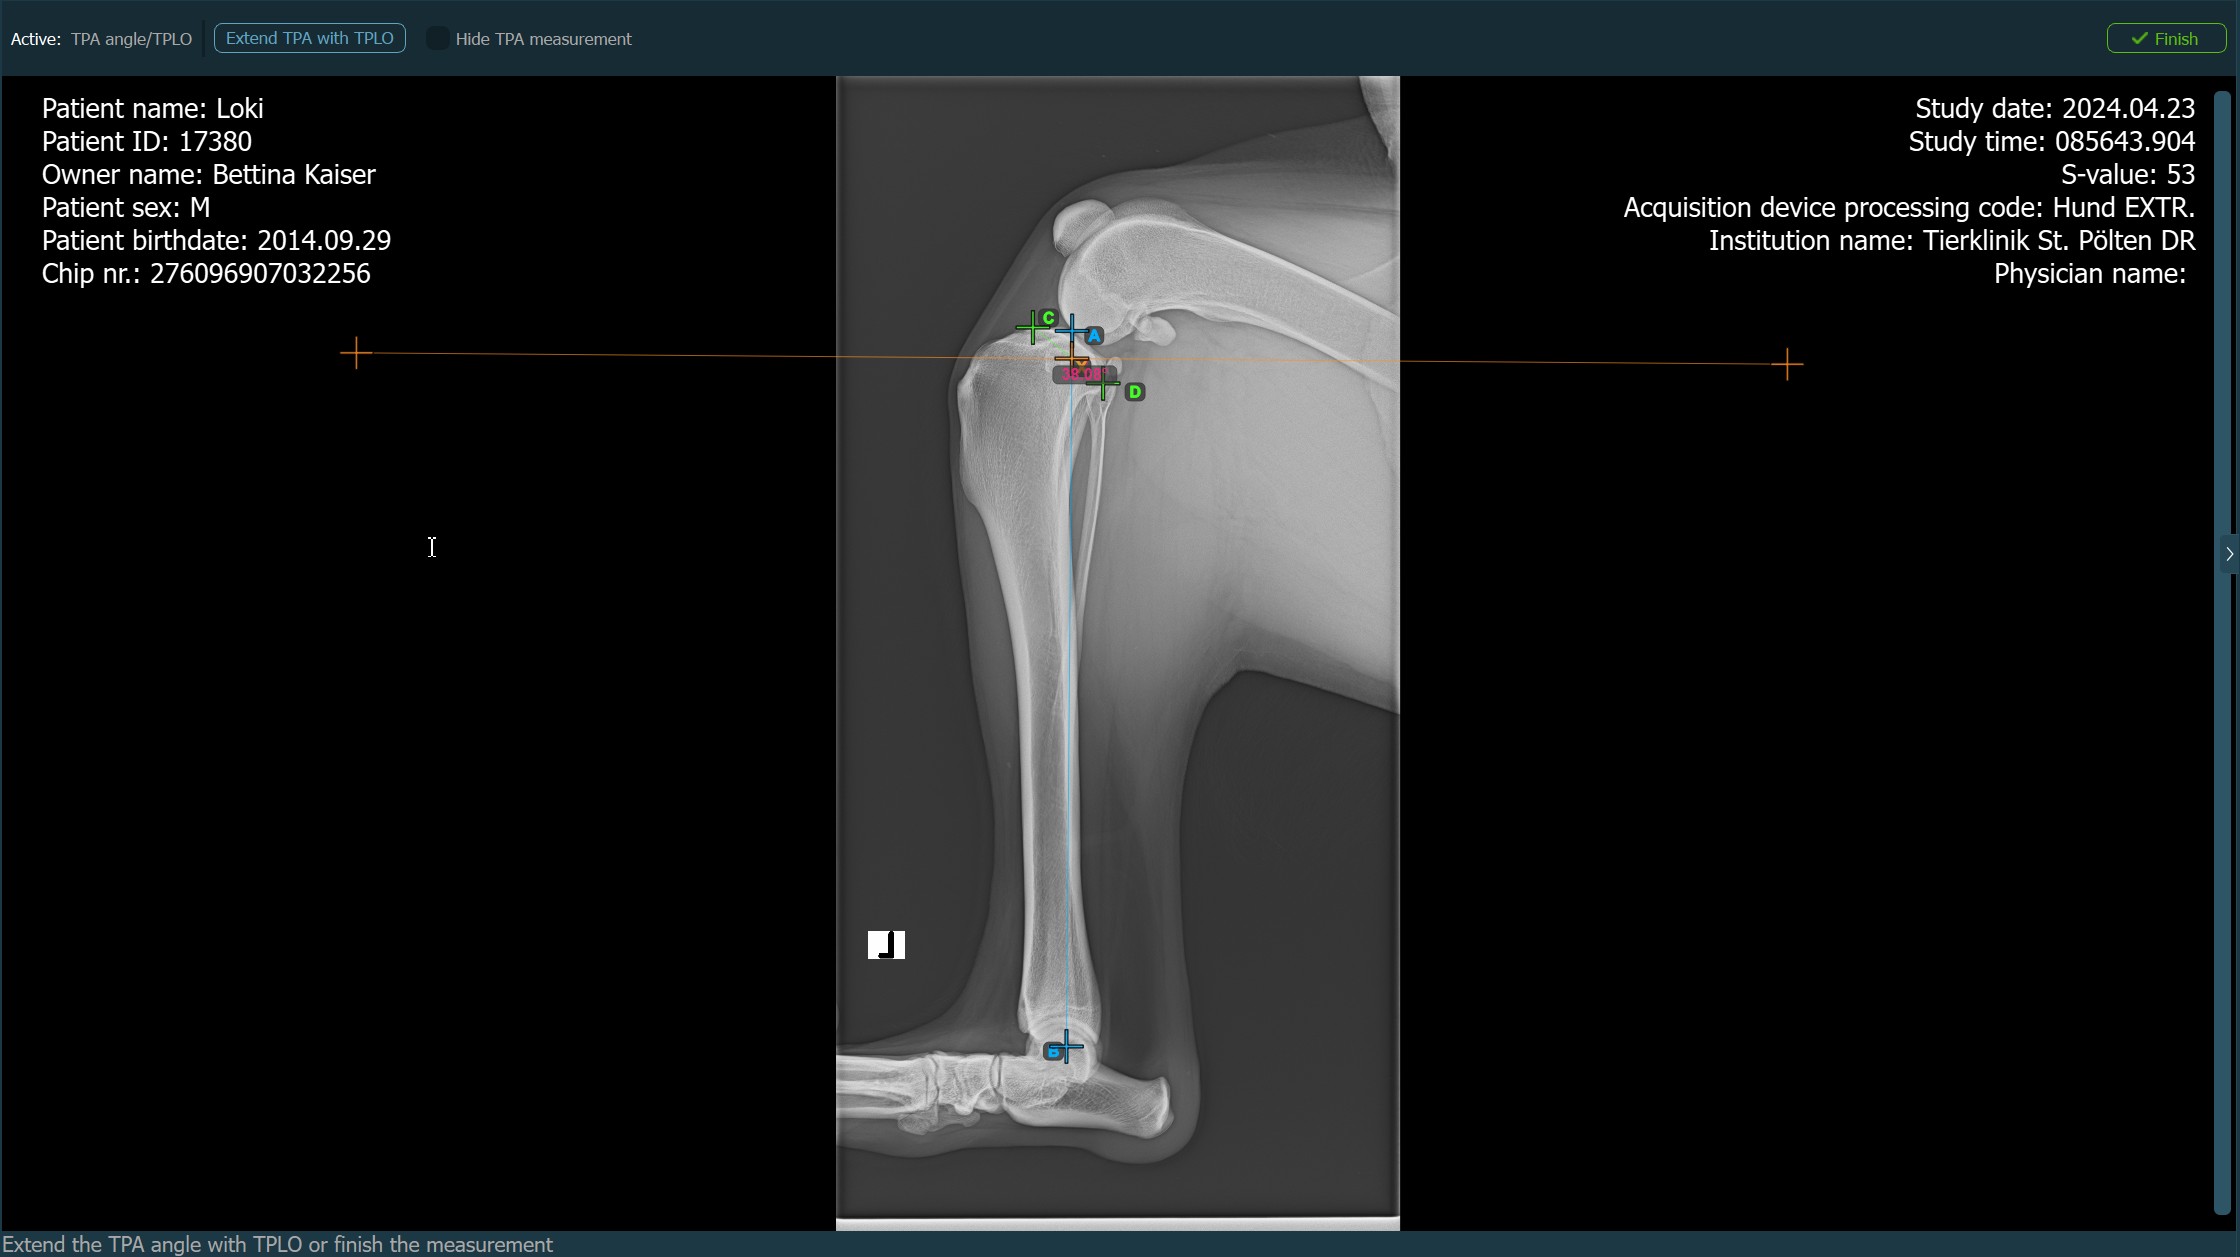

Der TPA-Winkel (Tibial Plateau Angle) ist eine der wichtigsten orthopädischen Messungen in der Veterinärmedizin und misst die Neigung des Tibiaplateaus relativ zur Längsachse der Tibia. Wählen Sie die Messung TPA-Winkel aus dem Erweiterten Messmenü und weisen Sie ihr die linke Maustaste zu.

Die TPA-Winkel-Messung ist ein entscheidender Bestandteil der Planung von Korrekturoperationen wie TPLO (Tibial Plateau Leveling Osteotomy). Erweitern Sie die TPA-Winkel-Messung mit TPLO in den Einstellungen des einfachen Viewers.

Starten Sie die Messung, indem Sie die Eminentia Intercondylaris markieren, die sich am Gelenk zwischen Femur und Tibia befindet.

Das Bild unten zeigt die übliche Platzierung des Punkts Eminentia Intercondylaris.

Fahren Sie fort, indem Sie den Mittelpunkts der Cochlea markieren, der sich am Ende des Tibiaknochens befindet. Die Linie zwischen der Eminentia Intercondylaris und dem Mittelpunkts der Cochlea stellt die Längsachse der Tibia dar.

Das Bild unten zeigt die übliche Platzierung des Mittelpunkts der Cochlea.